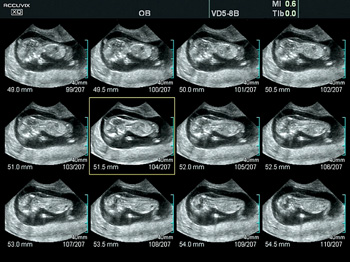

Объемная визуализация сердца плода. Эта впечатляющая функция исследования сердца плода основана на достижениях технологии 4D и связана с пространственно-временной корреляцией получаемого вами изображения. Теперь вы сможете сохранять полученные данные для

Автоматическое измерение основных параметров биометрии плода в акушерстве. Удобная в использовании функция данного УЗ аппарата позволит вам с большей эффективностью определить и выявить возможные отклонения при наблюдении за развитием плода во время берем

Ультразвуковая томография. Другое название данной функции, мультислайдинг, таит в себе ответ на вопрос о ее назначении. Данные, полученные вами во время первоначального трехмерного сканирования, пополняются за счет просмотра нескольких двухмерных срезов.